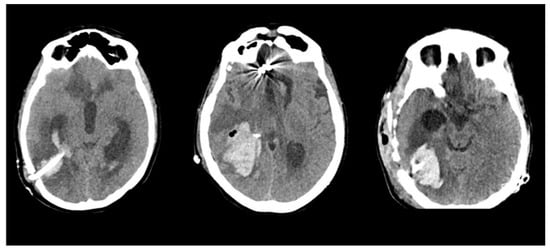

The present clinical series allowed us to draw a few considerations. All hemorrhagic complications observed in our series exhibited unusual characteristics in terms of timing, volume, and topography, as illustrated in Figure 5:

Figure 5.

Illustrative scans of three patients of the present series, showing the unusual complication of a delayed consistent hematoma surrounding the catheter pathway, and corresponding clinically to frank neurological deterioration.

- The location of the hematoma was consistently distant from the arteriovenous malformation (AVM) nidus, surrounding the trajectory of the ventricular catheter.

- The occurrence of the hemorrhagic complication transpired several weeks after the initial AVM rupture and several days after the placement of the VPS.

- Catheter-related DICH manifested in all 10 cases without any evident coagulation disorders or other identifiable risk factors.